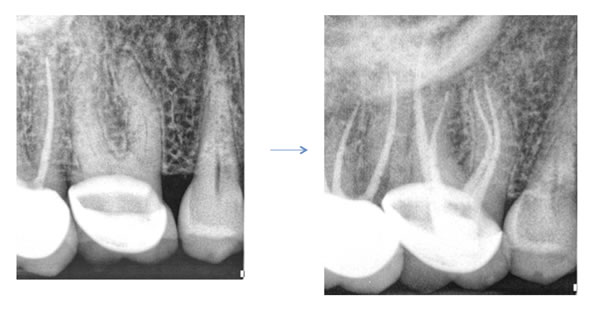

Historically the dental literature reported an occurrence of this canal to be found in about 60 percent of maxillary first molars and 30 percent of maxillary second molars. With the introduction of high magnification into the field, clinicians found this canal at a rate much higher than what was reported in the past. The higher occurrence has since been verified in the endodontic literature with reports of up to 93 % in first molars and 60 % in second molars (Stropko et al, JOE 1999). In order to optimize successful treatment of maxillary molars, finding and treating the MB2 canal is essential. This canal is often difficult to find and even harder to negotiate. I have included several guidelines below that I hope will help locate and treat these canals.

Do they meet? Many times the ML canal will join the MB. However, contrary to what we often hear, even if the canals meet, the untreated ML canal can adversely affect the outcome or long term success of the endodontic treatment. Finding both canals is crucial to complete endodontics on a maxillary first molar.